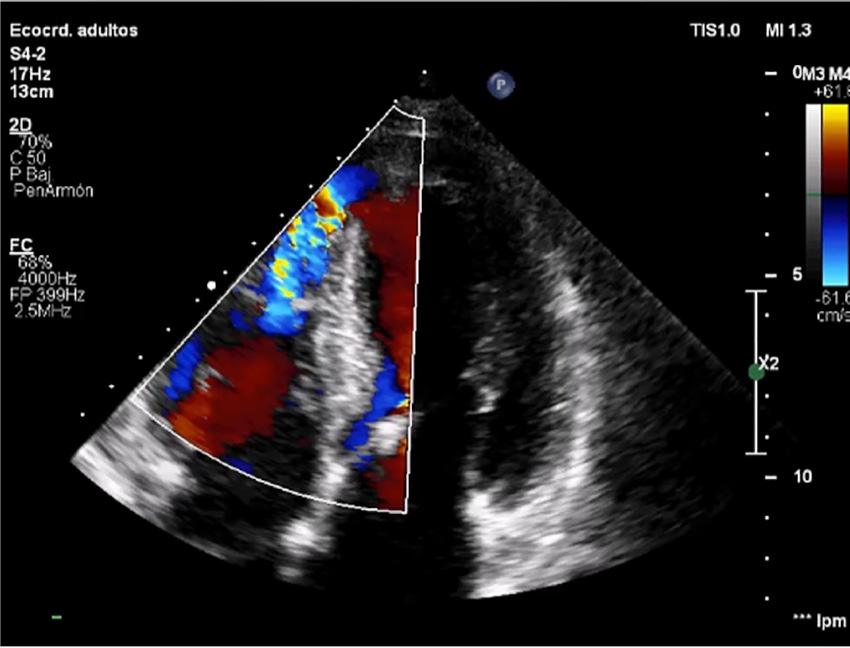

The patient remained stable until day 6, when she developed signs of decompensated heart failure. A new mesosystolic murmur at mitral focus was detected, which led to a new echocardiogram, revealing septal perforation in the apical septal segment with 12 mm diameter and 6 mm apical septum thickness (Figure 2).